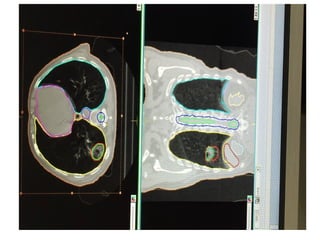

Non 4 D CT:The PTV will include the GTV plus an

additional 0.5 cm margin in the axial plane and 1.0 cm

margin in the longitudinal plane (craniocaudal).

4D CT-simulation: An internal target volume (ITV)

around the GTV, accounting for tumor motion may be

defined from the 4D CT dataset. The PTV will include the

ITV plus an additional 0.5 cm margin uniformly applied to

the ITV.

• Slice thickness : ≤ 3.0 mm

• OAR Contouring as follows: